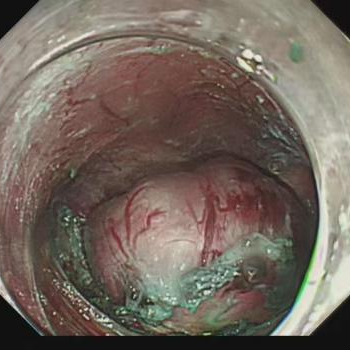

手术当天,在消化内科、内镜中心、麻醉医师和胸外科团队的共同努力下,最终通过微创治疗的方式为付先生完整切除了这颗大小约 3.5*5 cm 的「土豆」。术后第 5 天,付先生便顺利出院了。

杨叶医生提醒,随着胃镜普及,越来越多消化道的黏膜下肿瘤被发现。虽然多数为良性,但若瘤体较大、生长较快或位于特殊部位,仍建议积极干预。STER 手术作为超微创内镜下治疗技术,主要用于切除位于消化道黏膜下的病变,尤其适用于食管、胃、直肠等部位的黏膜下肿瘤,尤其适合瘤体直径 ≤ 3.5 厘米、未侵犯浆膜层的病变。